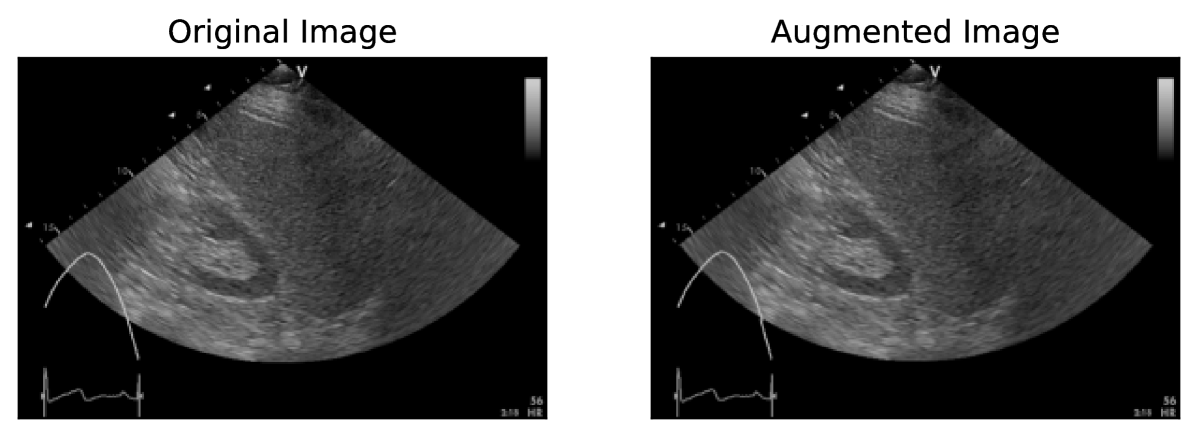

Refer to caption

Figure 7: The speckle reduction augmentation applied to an image from the AUL dataset with σspatial=1.0subscript𝜎spatial1.0\sigma_{\text{spatial}}=1.0italic_σ start_POSTSUBSCRIPT spatial end_POSTSUBSCRIPT = 1.0 and σcolor=1.0subscript𝜎color1.0\sigma_{\text{color}}=1.0italic_σ start_POSTSUBSCRIPT color end_POSTSUBSCRIPT = 1.0.

4.4 Speckle Reduction

Speckle noise is caused by interference between ultrasound waves. The speckle pattern observed in images captured using machines from different vendors often differs due to image enhancement and various filtering methods. As described in Ostvik et al. (2021), we apply a bilateral filter with randomly sampled parameter values to reduce the effect of these speckle patterns. We use the bilateral filter implementation from scikit-image (van der Walt et al., 2014). The σspatialsubscript𝜎spatial\sigma_{\text{spatial}}italic_σ start_POSTSUBSCRIPT spatial end_POSTSUBSCRIPT and σcolorsubscript𝜎color\sigma_{\text{color}}italic_σ start_POSTSUBSCRIPT color end_POSTSUBSCRIPT are sampled uniformly from the ranges [0.1,2.0)0.12.0[0.1,2.0)[ 0.1 , 2.0 ) and [0,1)01[0,1)[ 0 , 1 ), respectively. An example of this augmentation is shown in Fig. 7.